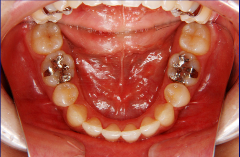

装置装着前

装置装着後

ステップ7.治療開始

※治療期間について

元の歯ならびの状態にもよりますが、通常約1年から2年ぐらいです。